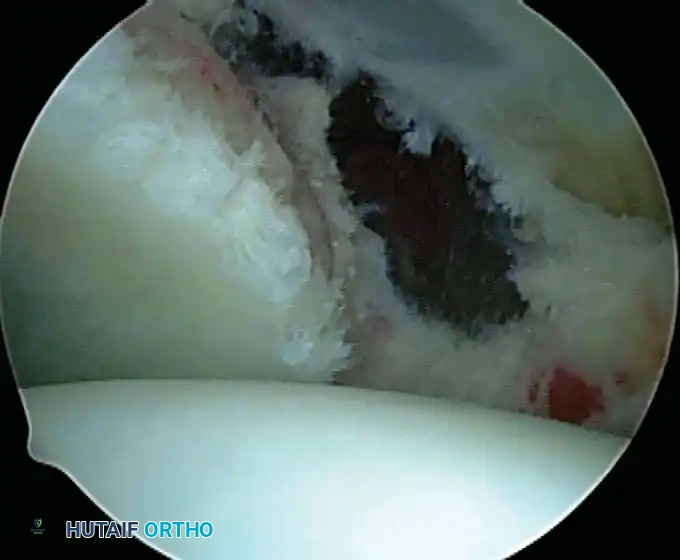

In the overhead throwing athlete, the shoulder is repeatedly placed in extreme abduction, hyperextension, and external rotation (the late cocking phase). This position forces the greater tuberosity and the undersurface of the rotator cuff to impinge against the posterosuperior glenoid rim and labrum. This internal impingement results in fraying of the cuff undersurface and the superior labrum. Repetitive microtrauma leads to anteroinferior ligamentous laxity and a "peel-back" of the posterosuperior capsular complex.

* Identification and extraction of loose bodies: Particularly those residing in the posterior recess, which are notoriously overlooked during open procedures.

* Evaluation of primary rotator cuff impingement: Assessing the tissue quality of the rotator cuff to determine the feasibility of an all-arthroscopic repair versus an open or mini-open approach.